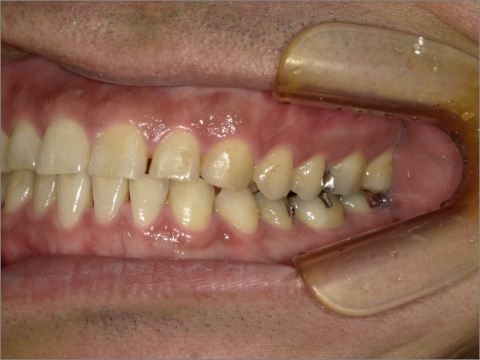

ご年齢 35歳男性 治療期間 2022/08/22〜2023/03/24(1年5ヶ月)

診断 110,000円(税込) アライナー 550,000円(税込) リテーナー 55,000円(税込)

ご年齢 35歳男性

治療期間 2022/08/22〜2023/03/24(1年5ヶ月)

診断 110,000円(税込)

アライナー 550,000円(税込)

リテーナー 55,000円(税込)

BEFORE

AFTER